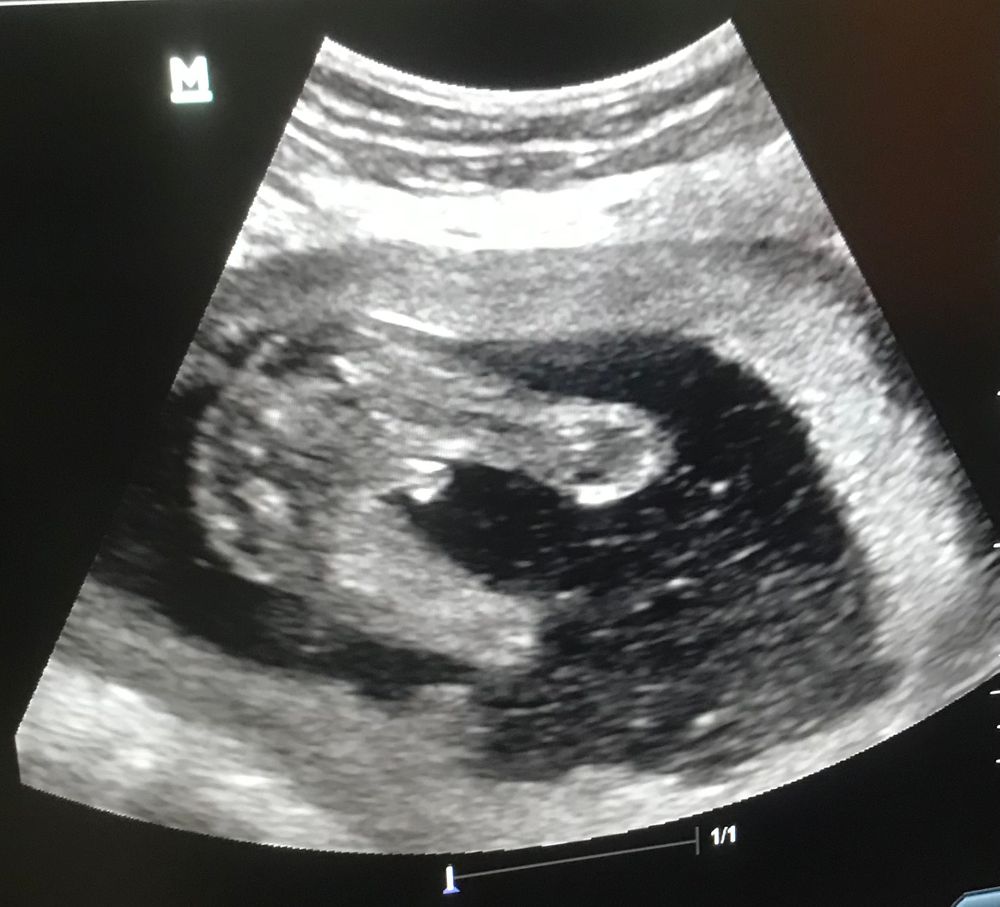

17 неделя, мальчик или девочка?

Кажется это яйки)

На первый взгляд похоже на мальчика, но яички у мальчика опускаются в мошенку к 30й неделе обычно, а в 18 недель они еще где то внутри там спускаются. А писюна на фото не видно. А что сказал врач? Я бы ему верила больше, в объеме все таки виднее, если аппарат нормальный.

Natali, сказали мальчик, но интуиция подсказывает что девочка

Какая тут девочка с таким хозяйством 🥴😁

Наталья, думаю может пуповина🥲